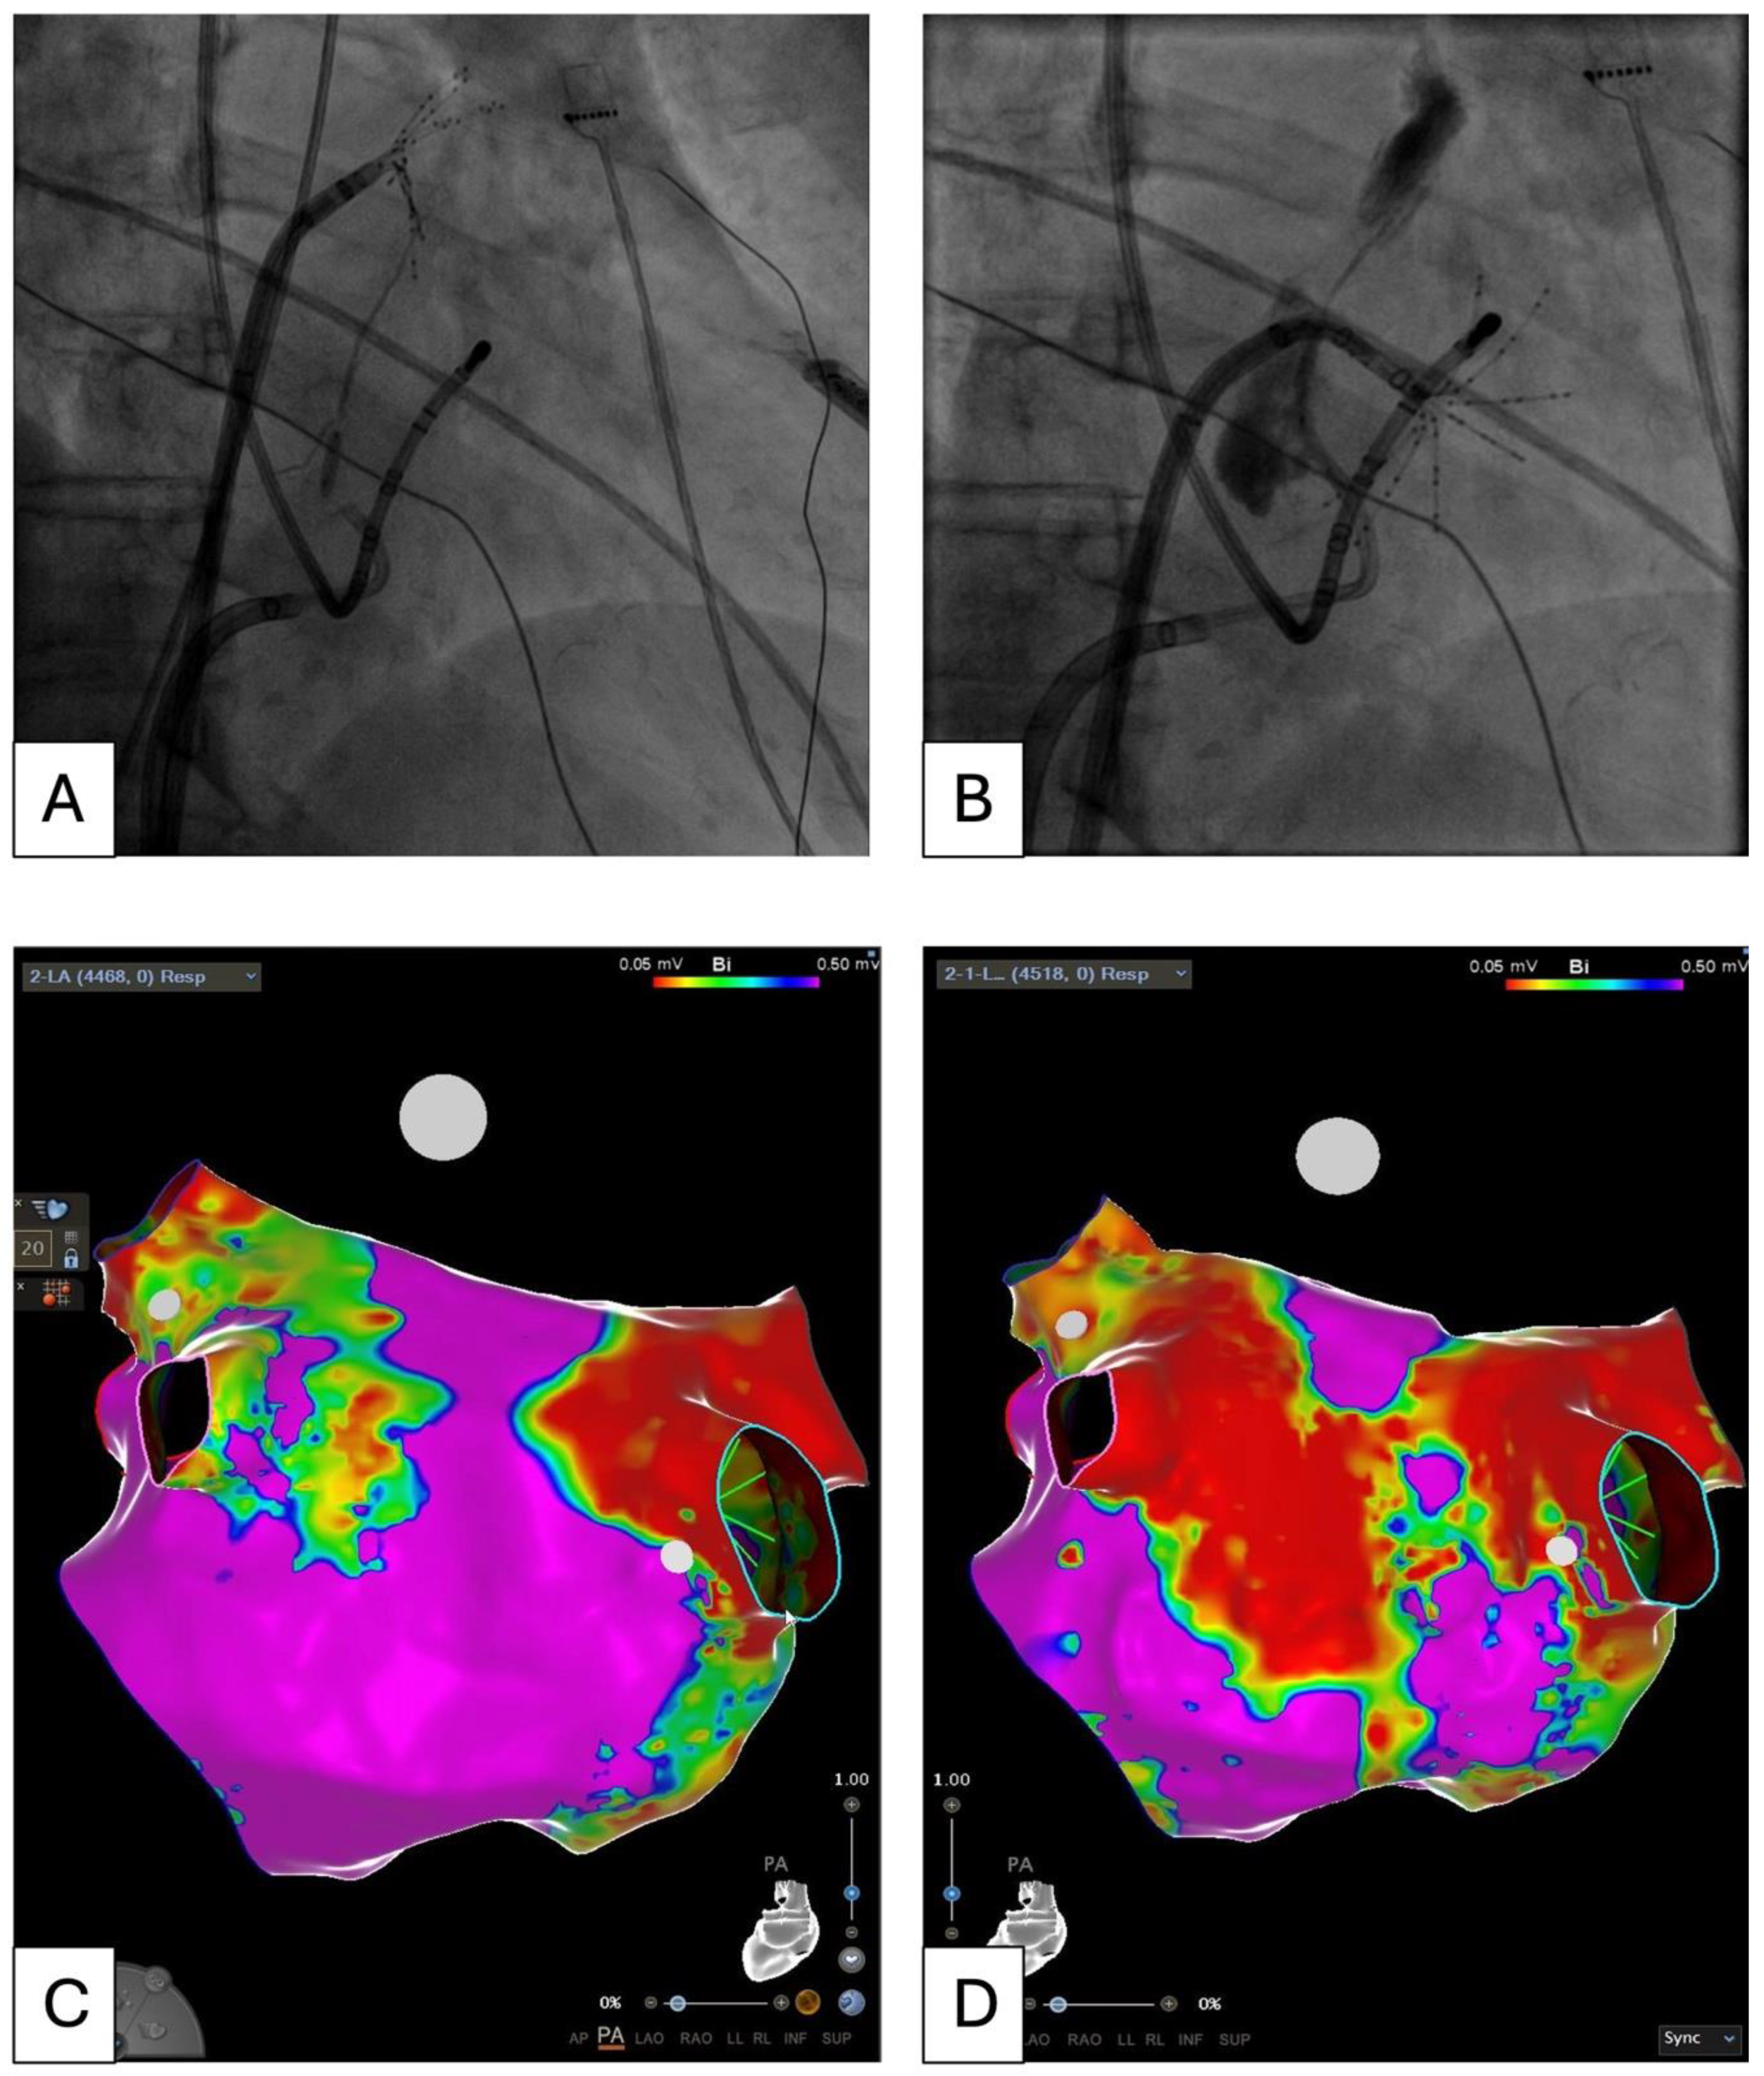

- Madaffari, A.; Knecht, S.; Spies, F.; Schaer, B.; Kühne, M.; Sticherling, C.; Osswald, S. Epicardial Connection: The Achilles Heel of Gap Mapping After Wide Antral Pulmonary Veins Isolation. JACC Clin. Electrophysiol. 2019, 5, 1356–1357. [Google Scholar] [CrossRef] [PubMed]

- Kueffer, T.; Tanner, H.; Madaffari, A.; Seiler, J.; Haeberlin, A.; Maurhofer, J.; Noti, F.; Herrera, C.; Thalmann, G.; Kozhuharov, N.A.; et al. Posterior Wall Ablation by Pulsed-Field Ablation: Procedural Safety, Efficacy, and Findings on Redo Procedures. Europace 2024, 26, euae006. [Google Scholar] [CrossRef]